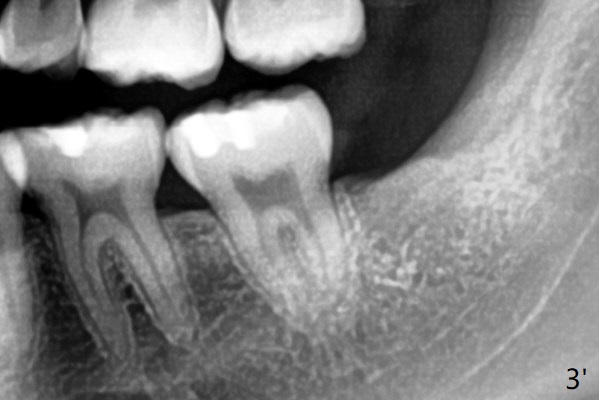

A 19-year-old man with history of orthodontic treatment (Fig.1,2) returns to office for #1,16,17,32 extraction with Collagen Plug placement at #17 and 32 (4-0 plain gut suture). The sockets heal in 4.5 months (Fig.3).